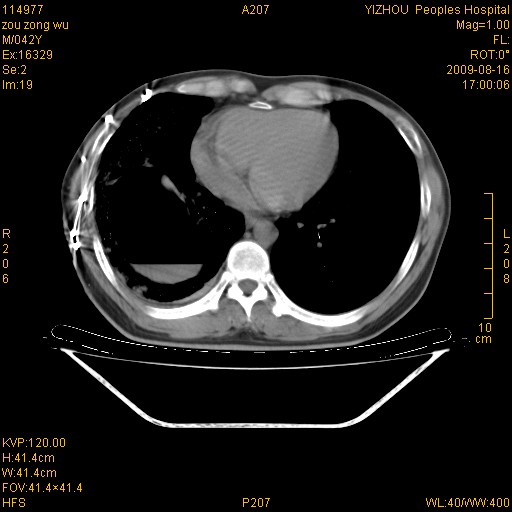

以下是引用zjzjr在2009-8-17 10:42:00的发言:[br]右侧间质性肺炎伴纤维化,右肺下叶肺囊肿伴感染(不除外外伤后引起),右肺野及胸壁软组织\\肝内见多发斑点状,中枪了吧.右侧胸膜肥厚\\粘连.